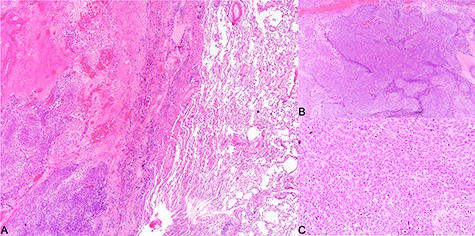

A repeat CT after TACE and PVE though showed sufficient hypertrophy of left liver, it also revealed significant growth of tumor with invasion to right lower lobe of lung through diaphragm (Fig. 1). Operation proceeded with a Mercedes-Benz incision with patient placed in supine position. Tumor was found to invade through medial part of diaphragm to right lower lobe of lung for 3 cm depth. Anterior approach right hepatectomy was performed [4]. Diaphragm was divided surrounding the tumor invasion site. En bloc wedge resection of the involved right lower lobe of lung was performed with endovascular staplers via the diaphragmatic opening. The diaphragmatic defect was closed with Goretex mesh (Fig. 2). Patient made an uneventful recovery and went home on Day 8 after surgery. Pathology confirmed a 12.5 cm poorly differentiated HCC invading through diaphragm to lung (Figs 3 and 4). Both resection margins at liver and lung were >1 cm. AFP decreased to 3 μg/l after operation.

Histological findings. (A) Tumor invading into lung parenchyma, (B) tumor arranged in solid sheets (×40) and (C) tumor cells of the poorly differentiated hepatocellular carcinoma (×200).